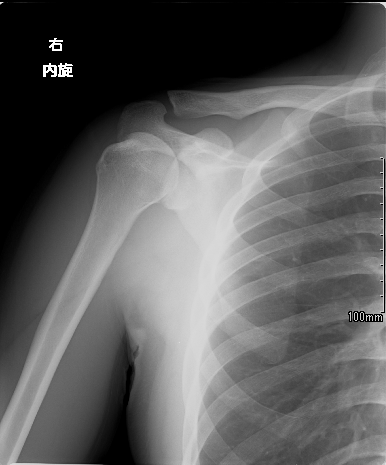

単純レントゲン撮影

X線(エックス線)を体にあてる(照射する)ことにより、画像化する検査です。空気は黒く、骨は白く見えます。一般的に『レントゲン撮影』と呼ばれます。